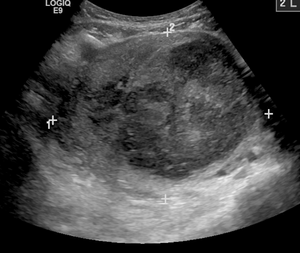

- Kidney cancer: kidney tumors such as renal cell carcinoma can be treated with image-guided ablation (RFA, MWA, cryotherapy) with similar results to partial nephrectomy. Generally, surgery via an either partial or total nephrectomy (removal of kidney) is most often curative but for patients with a smaller lesion or who are not ideal surgical candidates, radiofrequency or cryoablation ablation can be a curative option.[75] Advantages of cryoablation include the ability to visualize the ice ball as well as use more than one probe simultaneously to create the desired ice ball shape. Benign kidney tumors such as angiomyolipomas can be treated with transarterial embolization to shrink the tumor size and reduce the risk of rupture/bleeding. Other embolizations are also performed for symptom relief or prior to surgery to reduce bleeding.[76]